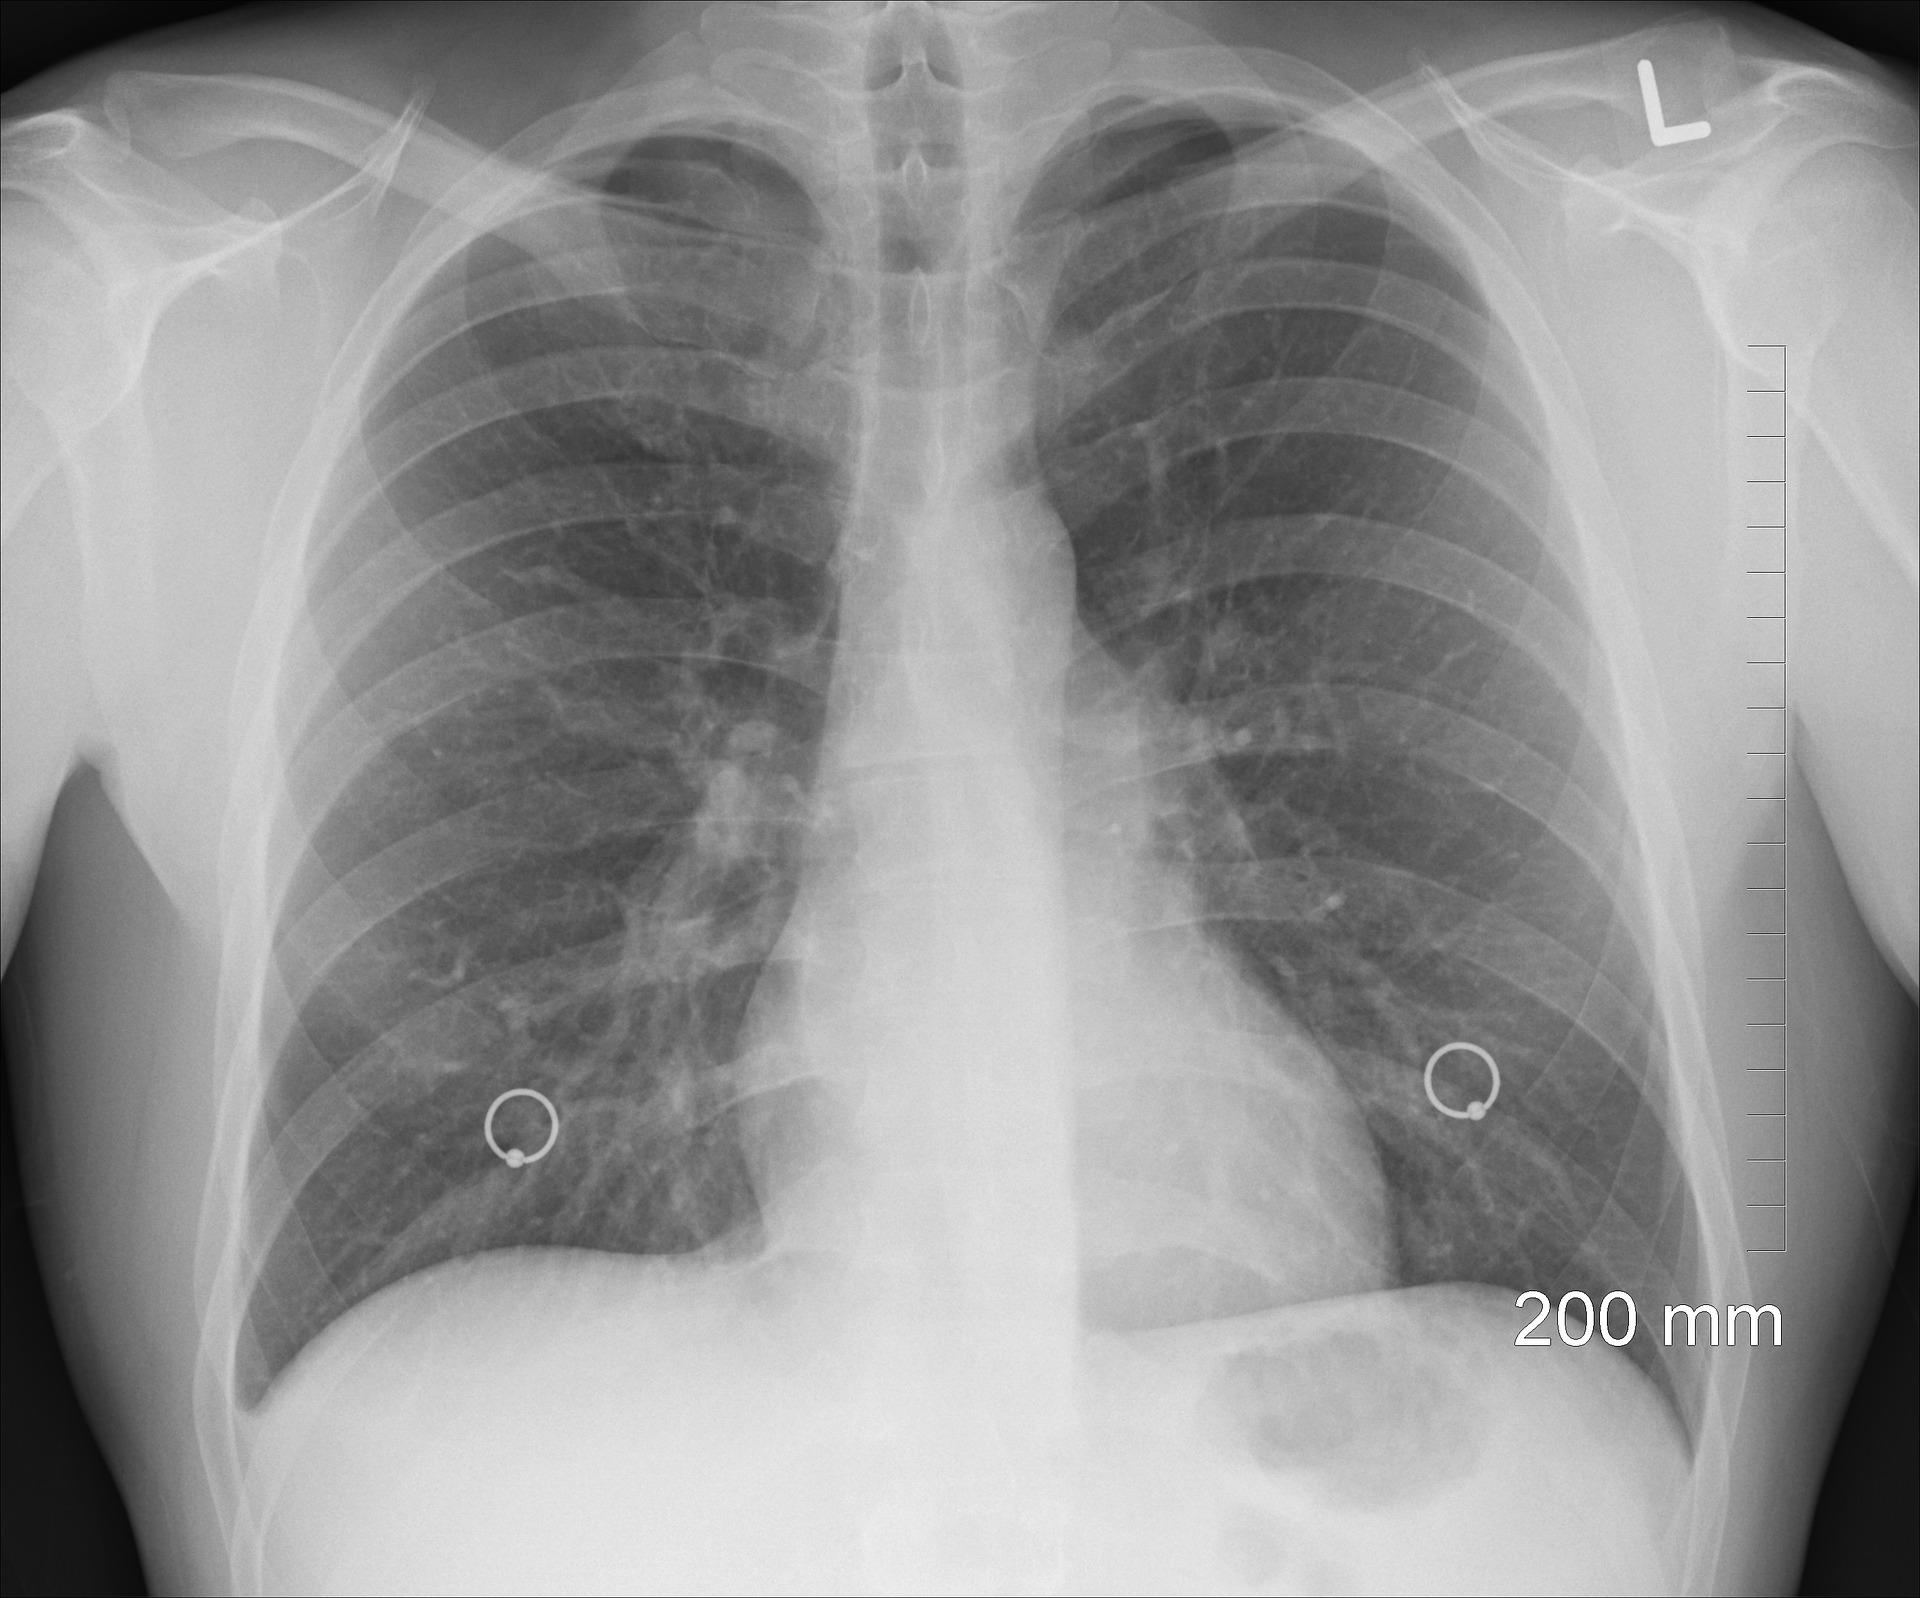

La Tuberculosis es una infección causada por una bacteria que afecta principalmente los pulmones. Sin embargo, también puede presentarse en otros órganos como la piel, el hígado, los riñones, los genitales y las meninges, entre otros.

Del total de casos registrados el año anterior 304 correspondieron a Tuberculosis pulmonar y 49 a Tuberculosis extrapulmonar.